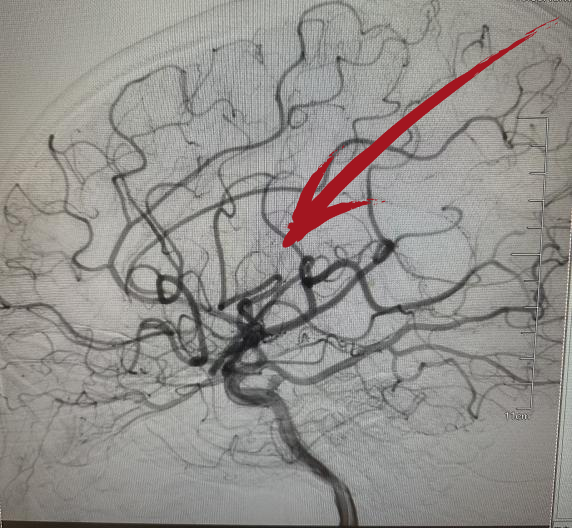

▲术后DSA提示右侧大脑中动脉已开通